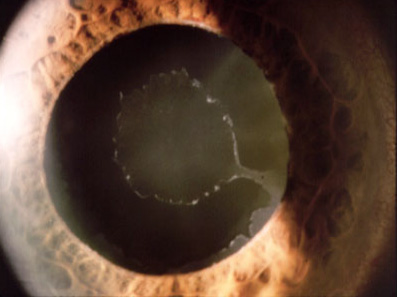

假性剥脱性青光眼图谱

假性剥脱性青光眼